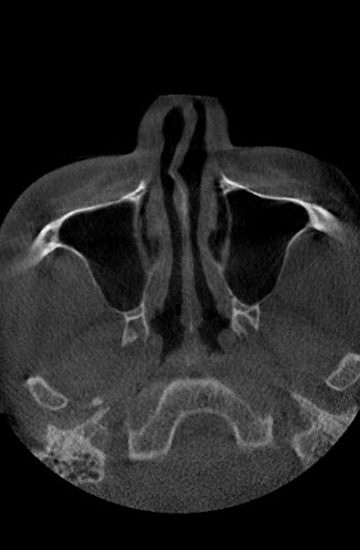

비중격만곡증이란?

비중격은 코를 둘로 나누는 벽으로,

휘거나 비틀리면 비중격만곡증이라 하며

C형·S형으로 구분되고 코막힘을 유발

• 비중격만곡증

정상 코

비중격만곡증 C형

비중격만곡증 S형

비중격만곡증의 증상

비중격이 휘면 공기 흐름이 막혀 코막힘이 생기며,

옆으로 누운 쪽 코가 막히는 증상이 발생